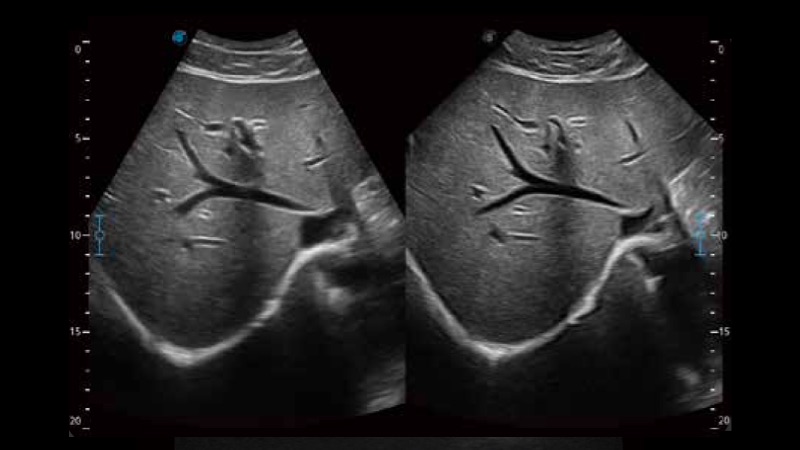

開立醫(yī)療通過不斷的技術(shù)創(chuàng)新,為大眾的生命健康提供持續(xù)關(guān)愛。P12 Plus采用全新一代超聲成像平臺,新平臺旨在將真實還原組織解剖結(jié)構(gòu)作為首要目標(biāo)。平臺采用全新集成化硬件模塊,搭載新一代芯片,系統(tǒng)性能得到大幅提升,為您的診斷提供了豐富的臨床信息。優(yōu)異的圖像表現(xiàn),豐富的探頭配置,全面的應(yīng)用功能,為您日常診斷提供了可靠的助手。

P12 Plus

彩色多普勒超聲診斷系統(tǒng)